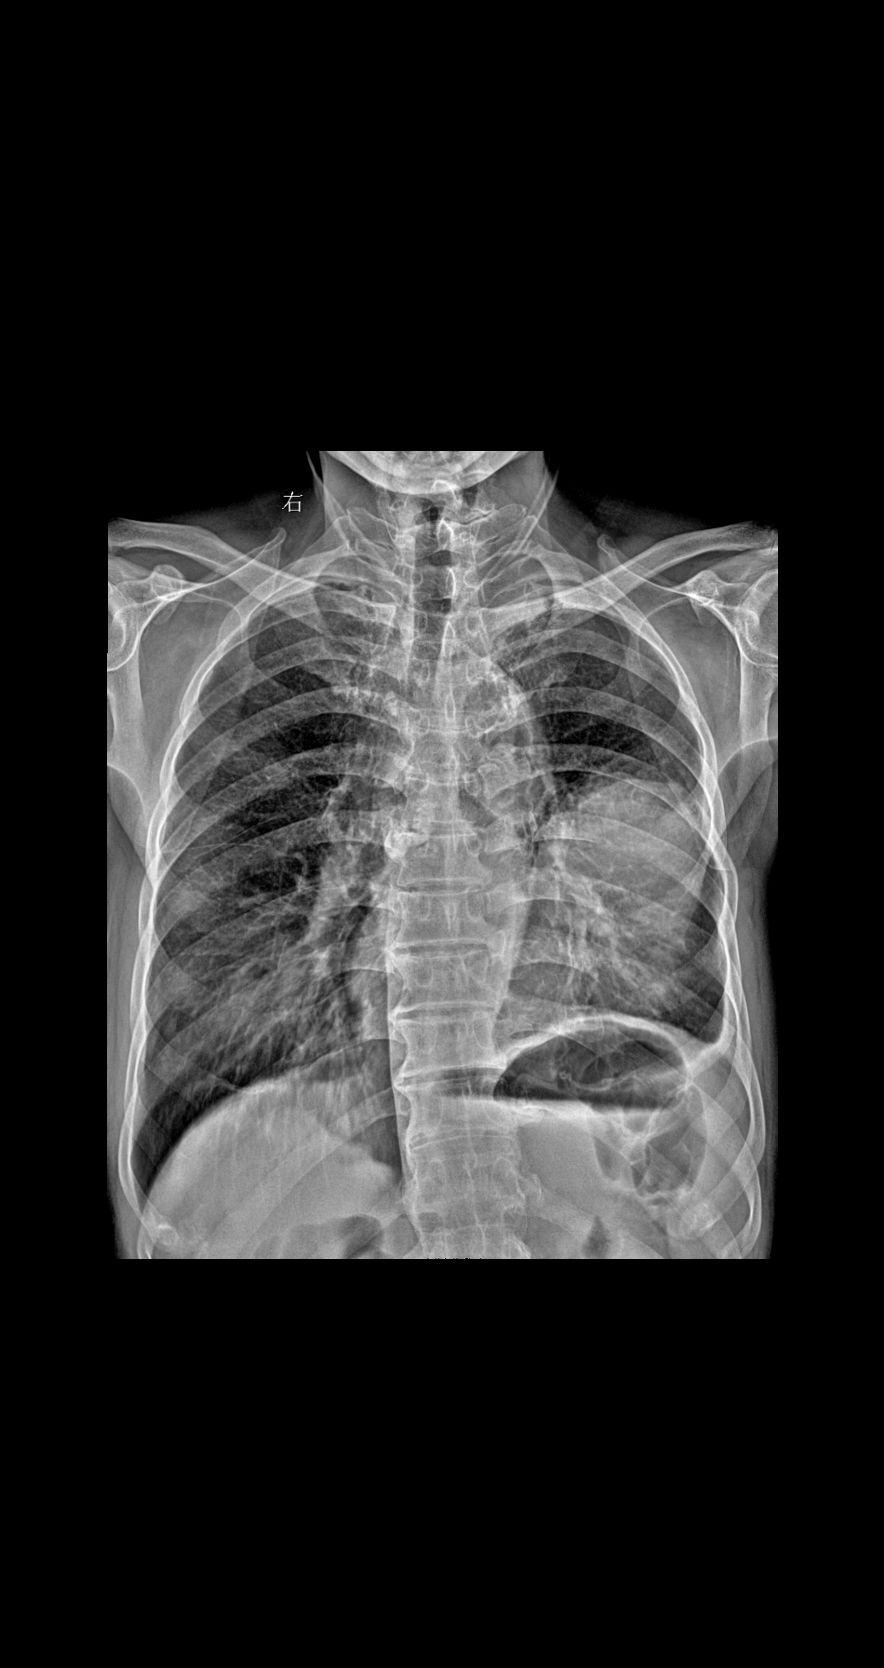

男 89岁 胸闷